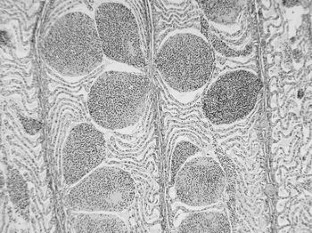

The aim of this study was to assess the effect of bifenthrin on common carp (Cyprinus carpio L.). The 96-h LC50 value of Talstar EC 10 (active substance 100 g l−1 bifenthrin) was found to be 57.5 μg l−1. Examination of haematological and biochemical profiles and histological tissue examination was performed on common carp after 96 h of exposure to Talstar EC 10 (57.5 μg l−1). The experimental group showed significantly higher (P < 0.01) values of plasma glucose, ammonia, aspartate aminotransferase and creatine kinase as well as the relative and absolute monocyte count, compared with the control group. Histological examination revealed teleangioectasiae of secondary gill lamellae and degeneration of hepatocytes. The bifenthrin-based Talstar EC 10 pesticide preparation was classified as a substance strongly toxic for fish.